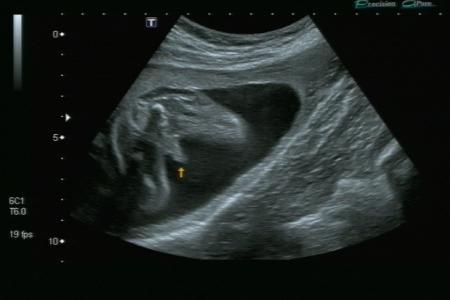

Nochmal ein foto ohne pullermann

Bild zu